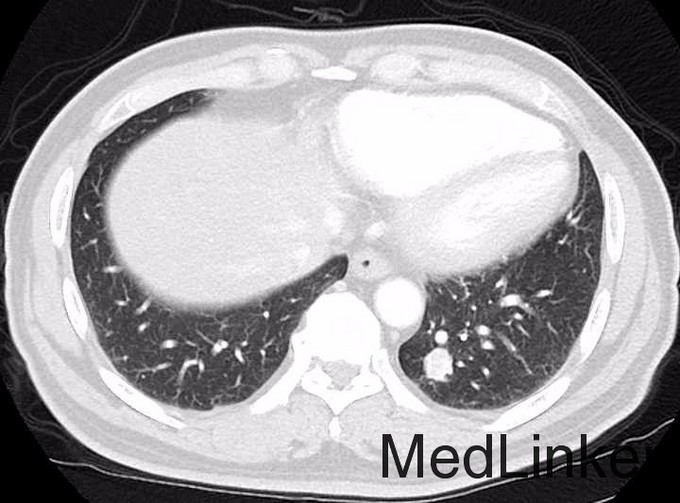

患者男,62岁,主因“右腰区疼痛半月余,入院检查发现双肺多发性占位性病变”收入院。 患者半月余前无明显诱因下出现右腰区疼痛,行腹部CT检查示:左侧肾上腺形态改变;左肾区条形软组织影,不除外萎缩或发育不良的左肾;于胸部CT结果示:左肺各叶、右肺上叶、中叶多发结节影

CT引导下穿刺活检,病理结果回报:穿刺肺组织可见癌浸润,结合形态学及免疫组化提示为透明细胞性肾细胞癌肺转移